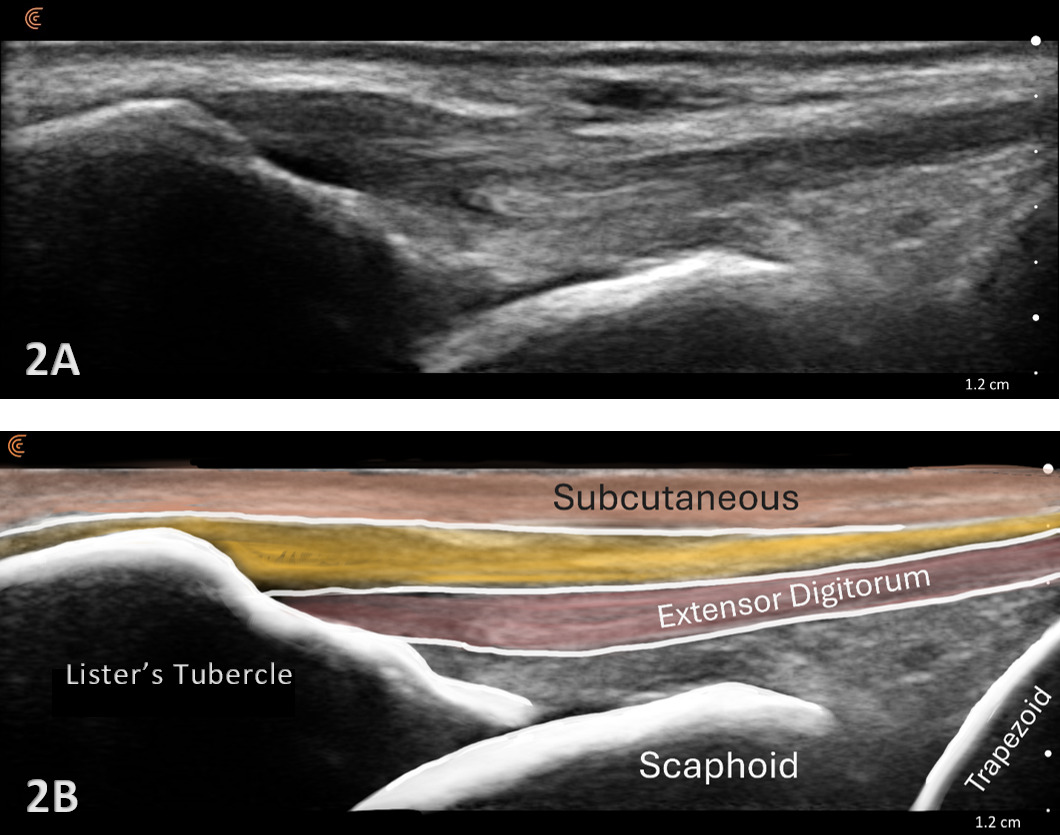

Patient Position: The patient is typically sitting with the volar forearm on the surface with the dorsal wrist facing superior. The dorsal surface is normally viewed as the structures are more superficial and easier to visualize. The transducer is placed in long axis (LAX) to view the radiocarpal joint, while, short axis (SAX) is used to view the scapholunate ligament.

Normal Sonographic Appearance

Typically, the radiocarpal joint is viewed in both the LAX and SAX. Typically, there is no joint effusion; therefore, the joint recess is collapsed or barely visible on ultrasound. The capsule should be thin and not distended. The dorsal ligaments are normally continuous and should exhibit a normal fibrillar pattern, indicating they are intact and healthy. The synovium is typically visualized as a very thin echogenic line, with no synovial hypertrophy. The articular surfaces of the radius and the carpal bones should include uniform anechoic or hypoechoic cartilage layers and demonstrate smooth, continuous hyperechoic cortical lines with no physical breaks or breaches.